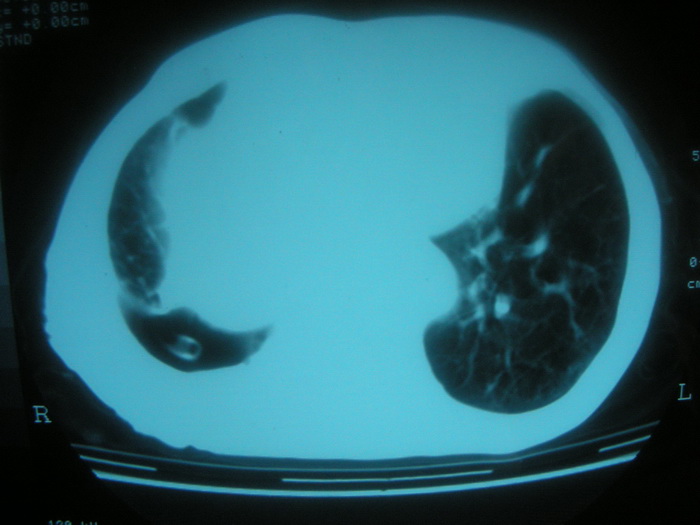

以下是引用卜一在2008-2-16 6:10:00的发言:[br]右肾增大,实质内明显见占位性病灶,并突出体外,密度不均匀。另双肺上叶见散在的斑片 索条及点状结节样致密影,右下肺门区不规则团块,右侧胸腔积液并形成局限性气胸。考虑:1 右肾癌。2 右肺门淋巴结转移及肺内 胸膜转移。3 右上肺陈旧结核。